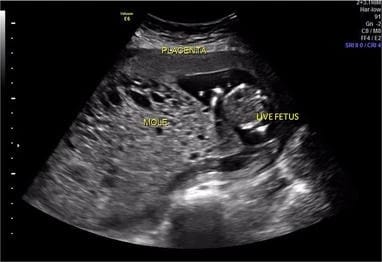

The ultra sound lady put the probe on my stomach and the look on her face quickly changed. I could see something in her eyes that didn't seem right. She asked me how far along I was and what were my symptoms and all kinds of questions as she kept taking pictures and moving all over my stomach. I asked her is the baby dead? I asked her if I could see.... she would not let me see, she would not tell me anything. She said wait untill the dr looks this over. That made me really confused. I told her I know I'm probley miscarrying could I please see.She would not let me. She then asked to do an internal ultra sound. I had no Idea what that was. She explained it to me and I said ok. I didnt really feel like I had a choice. She pushed the probe inside and pushed with all her might as she turned and moved it around to get pictures. She moved to the other side and did the same as I asked in pain and tears if she was finished. She made me put my fist under my back to hold my pelvis up high so she could get more diffrent pictures.It felt like an eternity. I then started to really cry out loud not only in pain but in fear as well. She asked if I was hurting I told her yes! She then proceeded to say I'm almost finished.

Finally the doctor came back in and explained that he seen that I had tissue that was not forming in the way it should have in the event of a pregnancy. He said I was in fact pregnant but it was growing tumors inside of my uterus instead of a baby.

My mind immediately went to my sister who had ovarian cancer. "Is it like cancer", I had asked. He said," it could be, we should take it out right away and test it and see what the next steps would be". I asked," well you said its tissue isn't all babies tissue and then it forms into a baby"? He replied "Not at this stage,If in fact you have been pregnant for 4 months it would not look like this". I cried "I had not even seen what it looked like". "She wouldnt let me see". They walked out of the room the nurse and doctor and started discussing something. I over heard them say "if we dont take it out now she will go home and it will come out or she will go to another hospital and we wont have it". One of the nurses then came in and asked me "what I wanted to do". I was confused and said I just want to go home. I was tired and couldn't think straight and full of confusion. She then left and came back in with a picture on her phone of my ultra sound that they had taken to show me what was in there. It was hard to believe that was really in there. I asked a couple of other questions to that nurse and then I agreed to go ahead with the D and C to get it removed. I definitely didn't want it to spread or make things worse. I called my best friend at the time ( the bosses wife) and she came with her children to take mine as I went through with the operation. It must have been midnight by then. I felt so bad to have to wake her and have her care for my children. I felt so bad my babies had to be in there with me to experience all of that with me. They were also scared.

The definition of a molar pregnancy is

A noncancerous tumor that develops in the uterus as a result of a nonviable pregnancy.

There may or may not be an embryo or placental tissue present. If there is an embryo, it unfortunately won't be able to survive.